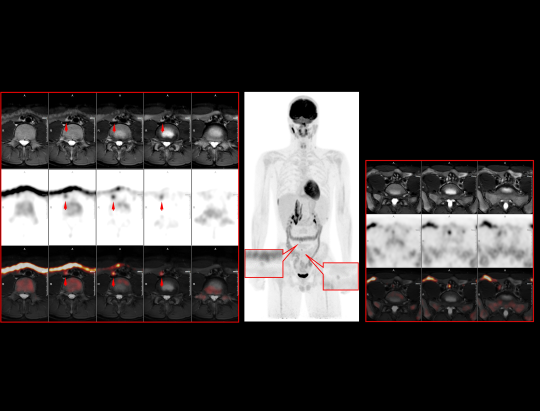

PET/MRI of the Breast  with a Lesion

Multi-parametric PET/MR for Comprehensive Breast Evaluation*

*Images Courtsey Of Nanjing First Hospital